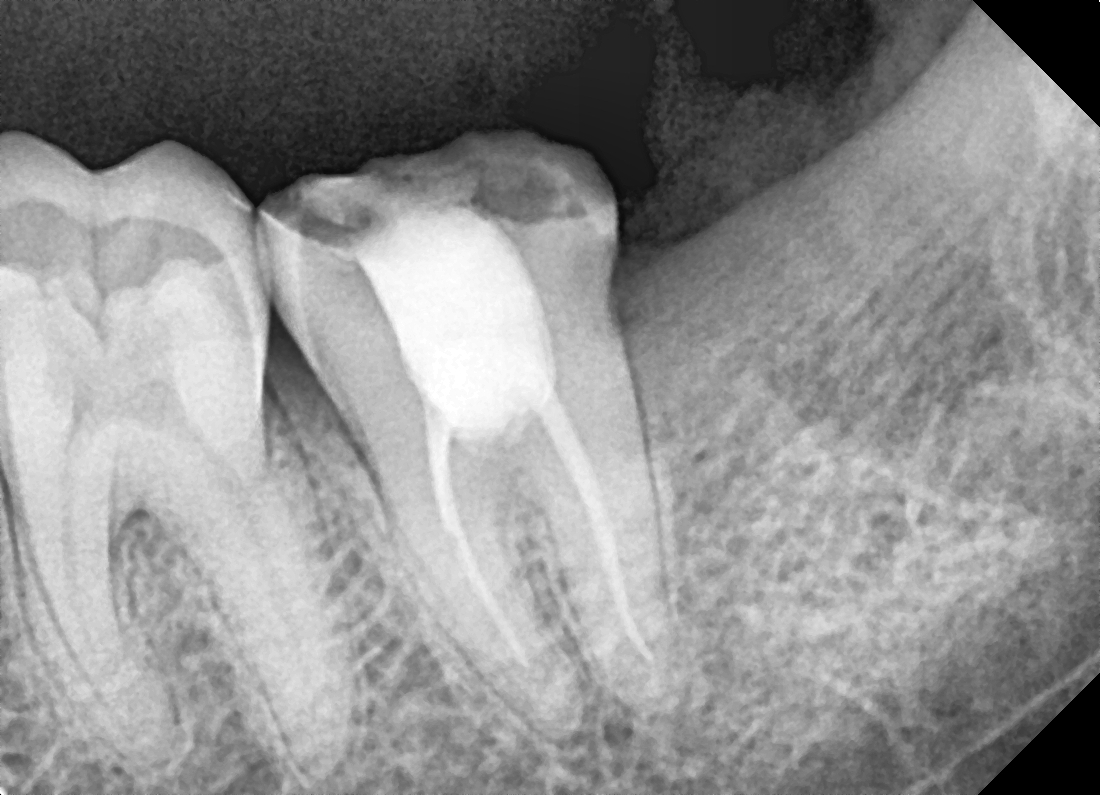

Lower 3rd Molar

After After

Before Before